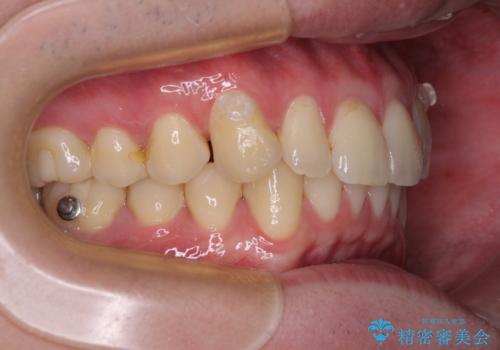

上下のデコボコを治したい インビザラインによる矯正治療

- 前歯のデコボコと突出感を気にして来院された患者様です。

極力目立たない装置を希望とのことで、インビザラインを用いて非抜歯で矯正治療を行うこととしました。

事前に親知らず4本を抜歯し、多少歯列を後方に移動できるように準備をした上で、なるべく歯と歯の間を削ることなくデコボコを解消できるように計画しました。

お仕事が忙しく、1日の装着時間は不十分となる日もありましたが、治療は順調に進めていくことができました。

途中、以前大きなむし歯で処置をした歯が痛み出し、根管治療が必要となったため、根管治療とオールセラミッククラウンによる補綴治療を行い、その後にインビザラインによる仕上げの歯列移動を行い、無事に治療を終えることができました。